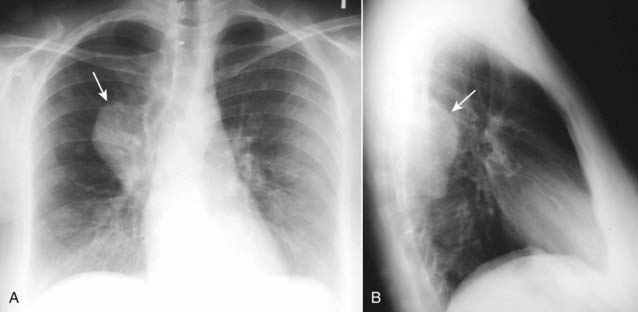

image

Figure 12-8 Middle mediastinal lymphadenopathy.

While lymphoma is the most likely cause of adenopathy in the middle mediastinum, other malignancies, such as small cell lung carcinoma and metastatic disease, as well as several benign diseases, can produce these findings. This patient has a mediastinal mass demonstrated on both the frontal (A) (solid white arrows) and lateral (B) views (solid black arrow). The mass is pushing the trachea forward (dotted white arrow) on the lateral view. The biopsied lymph nodes in this patient demonstrated small cell carcinoma of the lung.